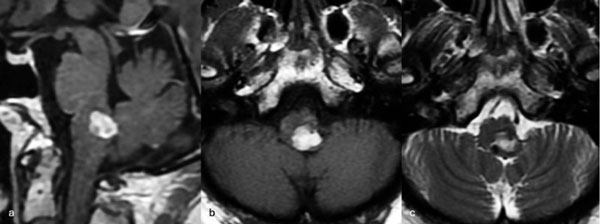

Caso 4: cavernoma bulbar

Una mujer de 53 años, con antecedentes de dos sangrados previos, consultó por un cuadro de perfil agudo caracterizado por tetraparesia asociada a compromiso de pares craneales bajos, que requirió instalación de una traqueostomía. La RM de encéfalo evidenció una malformación cavernomatosa en relación al bulbo izquierdo (Figura 9). Un mes después del último sangrado, la paciente fue sometida a una exéresis de la lesión mediante un abordaje suboccipital de línea media, vía intertonsilar (Figura 10), logrando una exéresis completa (Figura 11). Luego de la cirugía la paciente evolucionó con mejoría parcial de sus síntomas de ingreso, sin agregar nuevos déficits neurológicos.

Figura 9. RM preoperatoria de encéfalo. Se evidencia una lesión única intraaxial bulbotrigonal izquierda, que contacta la mitad inferior del piso del cuarto ventrículo, hiperintensa en T1 y T2, con vacíos de flujo que impresionan provenir de una malformación del desarrollo venoso, lo que sugiere una malformación cavernomatosa. A) Imagen en corte sagital ponderada en T1 posterior a la administración de gadolinio. B y C) Imágenes en corte axial ponderadas en T1 y T2, respectivamente.